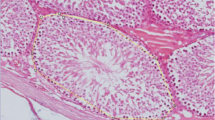

The testicular weight, epididymal spermatozoa, and fertility of mice after the treatment period in four groups are summarized in Table 3. At day 60, in Group C there was significant decreases in body weight, absolute and relative testicular weights, and epididymal spermatozoa counts when compared to those in the Group A. Further, a marginal recovery in body weight and all reproductive parameters were observed at day 120, but on day 150 further decreases in all parameters were noted in this group. Based on histological examinations of the testes (Fig. 2a–d), some atrophic seminiferous tubules with disrupted spermatogenesis were recognized in the testes (Fig. 2c). In sharp contrast, in the Group D, significant recoveries in body weight, epididymal spermatozoa counts, and fertility rates were observed at day 150, although absolute and relative testicular weights did not reach control levels (Table 3). All stages of germinal epithelium maturation, from spermatogonia to spermatozoa were shown in group D in testicular sections showing many normal-appearing seminiferous tubules (Fig. 2d).

Effect of TJ107 on testes histology after irradiation. Asterisks indicates the damaged seminiferous tubules with azoospermia in Group C c at day 120. However, in the Group D d, all stages of maturation of the germinal epithelium are seen in normal-appearing seminiferous tubules like in Group A a and Group B b. Bar = 50 μm